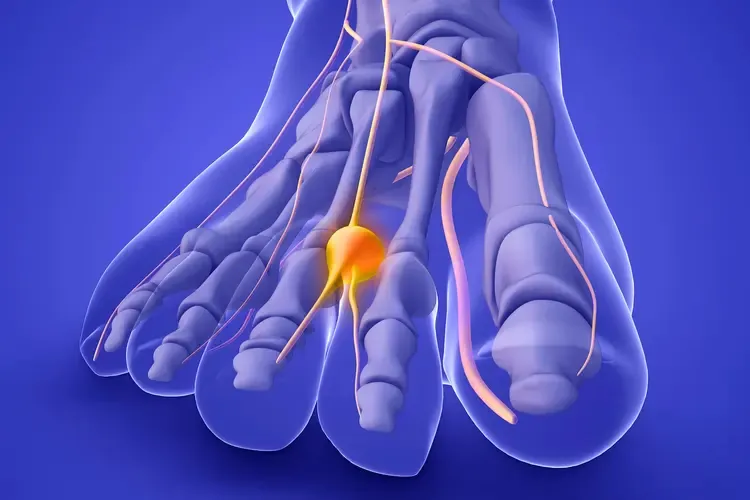

Neuroma de Morton

El neuroma de Morton es un engrosamiento del nervio interdigital, generalmente entre el 3º y 4º dedo. Provoca un dolor muy característico que muchos pacientes describen como “una descarga eléctrica”.

Síntomas característicos:

- Dolor quemante o punzante entre los dedos

- Sensación de tener una piedra o un bulto dentro del pie

- Hormigueo o entumecimiento en los dedos afectados

- Dolor que empeora al caminar y mejora al descalzarse

- Alivio temporal al masajear la zona

Factores de riesgo: Uso de tacones altos o calzado de punta estrecha, sobrecarga repetitiva (corredores, bailarines), pie plano o cavo, y alteraciones biomecánicas.